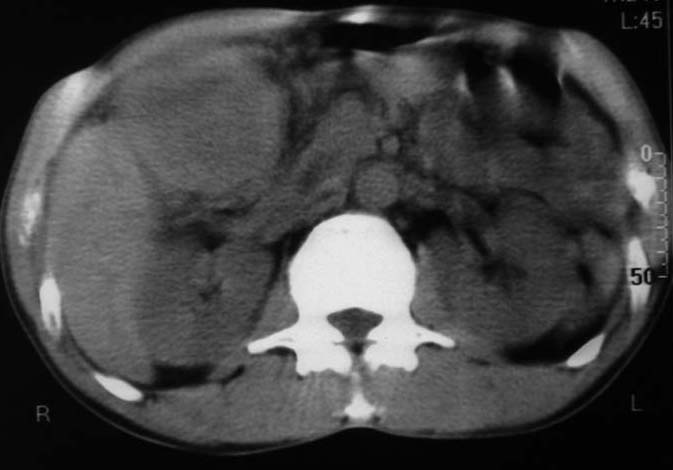

男,50y,右上腹包块痛10天,查:右上腹饱满,右肋下触及6*6cm大小包块,质硬,压痛。患者诉:10天前感冒胸闷,痛,后痛及右上腹部,既往有肝炎病史。

没有增强!只能考虑左叶内侧段巨块型肝癌(外生型)可能性大;胆囊呢?不除外胆囊癌累及肝脏。

病变位于胆囊窝内,其内密度不均,肝总管及胆总管扩张,胃里面没有清水充盈,不解为什么楼主不做好了准备再做呢,支持:“左叶内侧段巨块型肝癌(外生型)可能性大;不除外胆囊癌累及肝脏”建议增强吧。

我跟认为胆囊病变的可能性大,肠道准备不好,带来相关解剖结构的部位清晰。